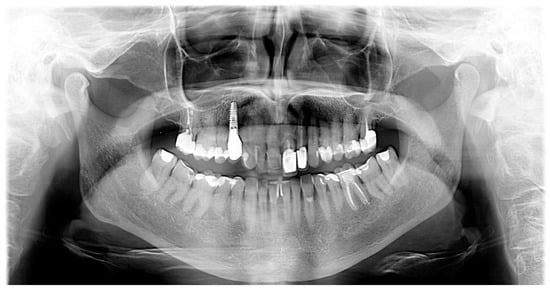

A three-dimensional iTero scan (iTero Element, Align Technology, San Jose, CA, USA), extraoral and intraoral photos using the dedicated application Invisalign Practice App (Align Technology, San Jose, CA, USA) as well as a pantomogram were taken during the visit.

The intraoral examination showed numerous porcelain restorations, including an implant, which excluded the possibility of orthodontic treatment with a fixed appliance—due to the difficult or sometimes impossible to obtain adhesion of the brackets to the crowns. The mobility of the tooth was a problem, which made eating difficult. The history did not reveal the presence of factors contributing to periodontitis, such as smoking, diabetes, stress and obesity. Current general blood tests presented by the patient were normal (morphology and vitamin D3 level). The periodontal examination showed no pockets deeper than 4 mm (measured with a periodontal probe scaled every 1 mm at six measurement points around each tooth). There was also no omission of the implant during treatment with the continuous arch method and no bleeding on probing (BOP). The modified Sulcus Bleeding Index (mSBI) was also 0. A very good level of oral hygiene was observed during treatment—20% according to the Approximal Plaque Index (API). Tooth 21 showed the second degree of mobility in the three-degree Miller Index scale—that is, vestibule-oral cavity proper mobility not exceeding 1 mm. The dental X-ray showed bone loss along ½ of the length of the root, except for the mesial surface where the bone level was normal. The tooth underwent endodontic treatment in the past—the X-ray image showed a partially filled canal without periapical changes. Clinical attachment loss (CAL) on the labial surface was 3 mm and the periodontal probing depth (PPD) was 4 mm. Tooth 21 and the adjacent tooth 22 were covered with zirconium oxide crowns. The patient also had a perfectly functioning dental implant in position 14. The patient did not consent to the CBCT examination. The diagnosis was based on an intraoral examination, scan, dental and panoramic radiographs as well as intra- and extraoral images.

- Pretreatment occlusion scan using the iTeroTM 5.0 scanner, extracted into OrthoCAD 5.9.1.50 software (Align Technology, San Jose, CA, USA) (Figure 4), extra- and intraoral images taken with the Invisalign Practice App (Align Technology, San Jose, CA, USA) and pantomogram (Figure 5). Based on the iTeroTM 3D scan (Align Technology, San Jose, CA, USA) and occlusal examination, it was decided to use the Invisalign® system (Align Technology, San Jose, CA, USA) with the Express 1 arch subtype—the shortest possible treatment with seven aligners (and seven additional aligners) involving only the upper arch because the aim was to eliminate the occlusal injury of one tooth by its intrusion and a change of the anterior–posterior and mesiodistal inclination. The first treatment plan was performed using the ClinCheck 6.0 software (Align Technology, San Jose, CA, USA), which assumed movements of tooth 21—the main movement was a palatal inclination of the crown by 4.4 degrees, a distortion by 3.3 degrees and an intrusion by 0.4 mm (Figure 6). The analysis of this plan showed that it was impossible to eliminate the traumatic occlusion when changing the position of only one tooth in the arch (Figure 7)—the analysis showed numerous abnormal occlusal contacts.

Figure 5. Pantomogram—visible porcelain restorations and an implant in area 14.

Periodontal status and oral hygiene were regularly monitored during treatment. Professional teeth cleaning was performed every 3 months. After obtaining the correct position of the teeth, thermoformable splint retention treatment was applied and the occlusion was rechecked for possible traumatic nodes. There were improvements in tooth stabilization (mobility of the first degree on the Miller scale) and the position of the connective tissue attachment on the labial surface—CAL—2 mm and PPD also 2 mm. The patient was not referred for re-endodontic treatment of the tooth since the previous root canal treatment was surely carried out according to the most modern standards at that time—under a microscope, filled with liquid gutta-percha—the gaps in the canal visible on the X-ray are not due to incomplete filling—the canal was obliterated, probably due to tooth trauma in childhood and the slow death of the pulp inside the tooth.

The presented report is intended to show the possibility of treating a case that may not be qualified by a general dentist for orthodontic treatment in the first reflex and adding a clear aligner treatment might not be the first idea. As it is shown, the treatment has been an effective, long-term approach to the treatment of an elderly patient. The authors’, and at the same time the attending physician’s, main concern was the maintenance of the retention phase. The patient must remember about the retention splint, if she forgets about it for 2–3 days, she feels stress on the tooth that has previously been seriously displaced. This is, of course, a normal process after orthodontic treatment but the effects of the tooth being subjected to jiggling forces are the greatest threat in terms of orthodontic resorption of the already shortened root. As for the case report itself, the reacher X-ray documentation, including CBCT, should be provided. However, taking into account the process of treatment and diagnosis itself, it was sufficient for its use. It is also necessary to continue the check-up visits so that we can still ensure 100 per cent health success, which the authors consider lifelong maintenance of the patient’s tooth.